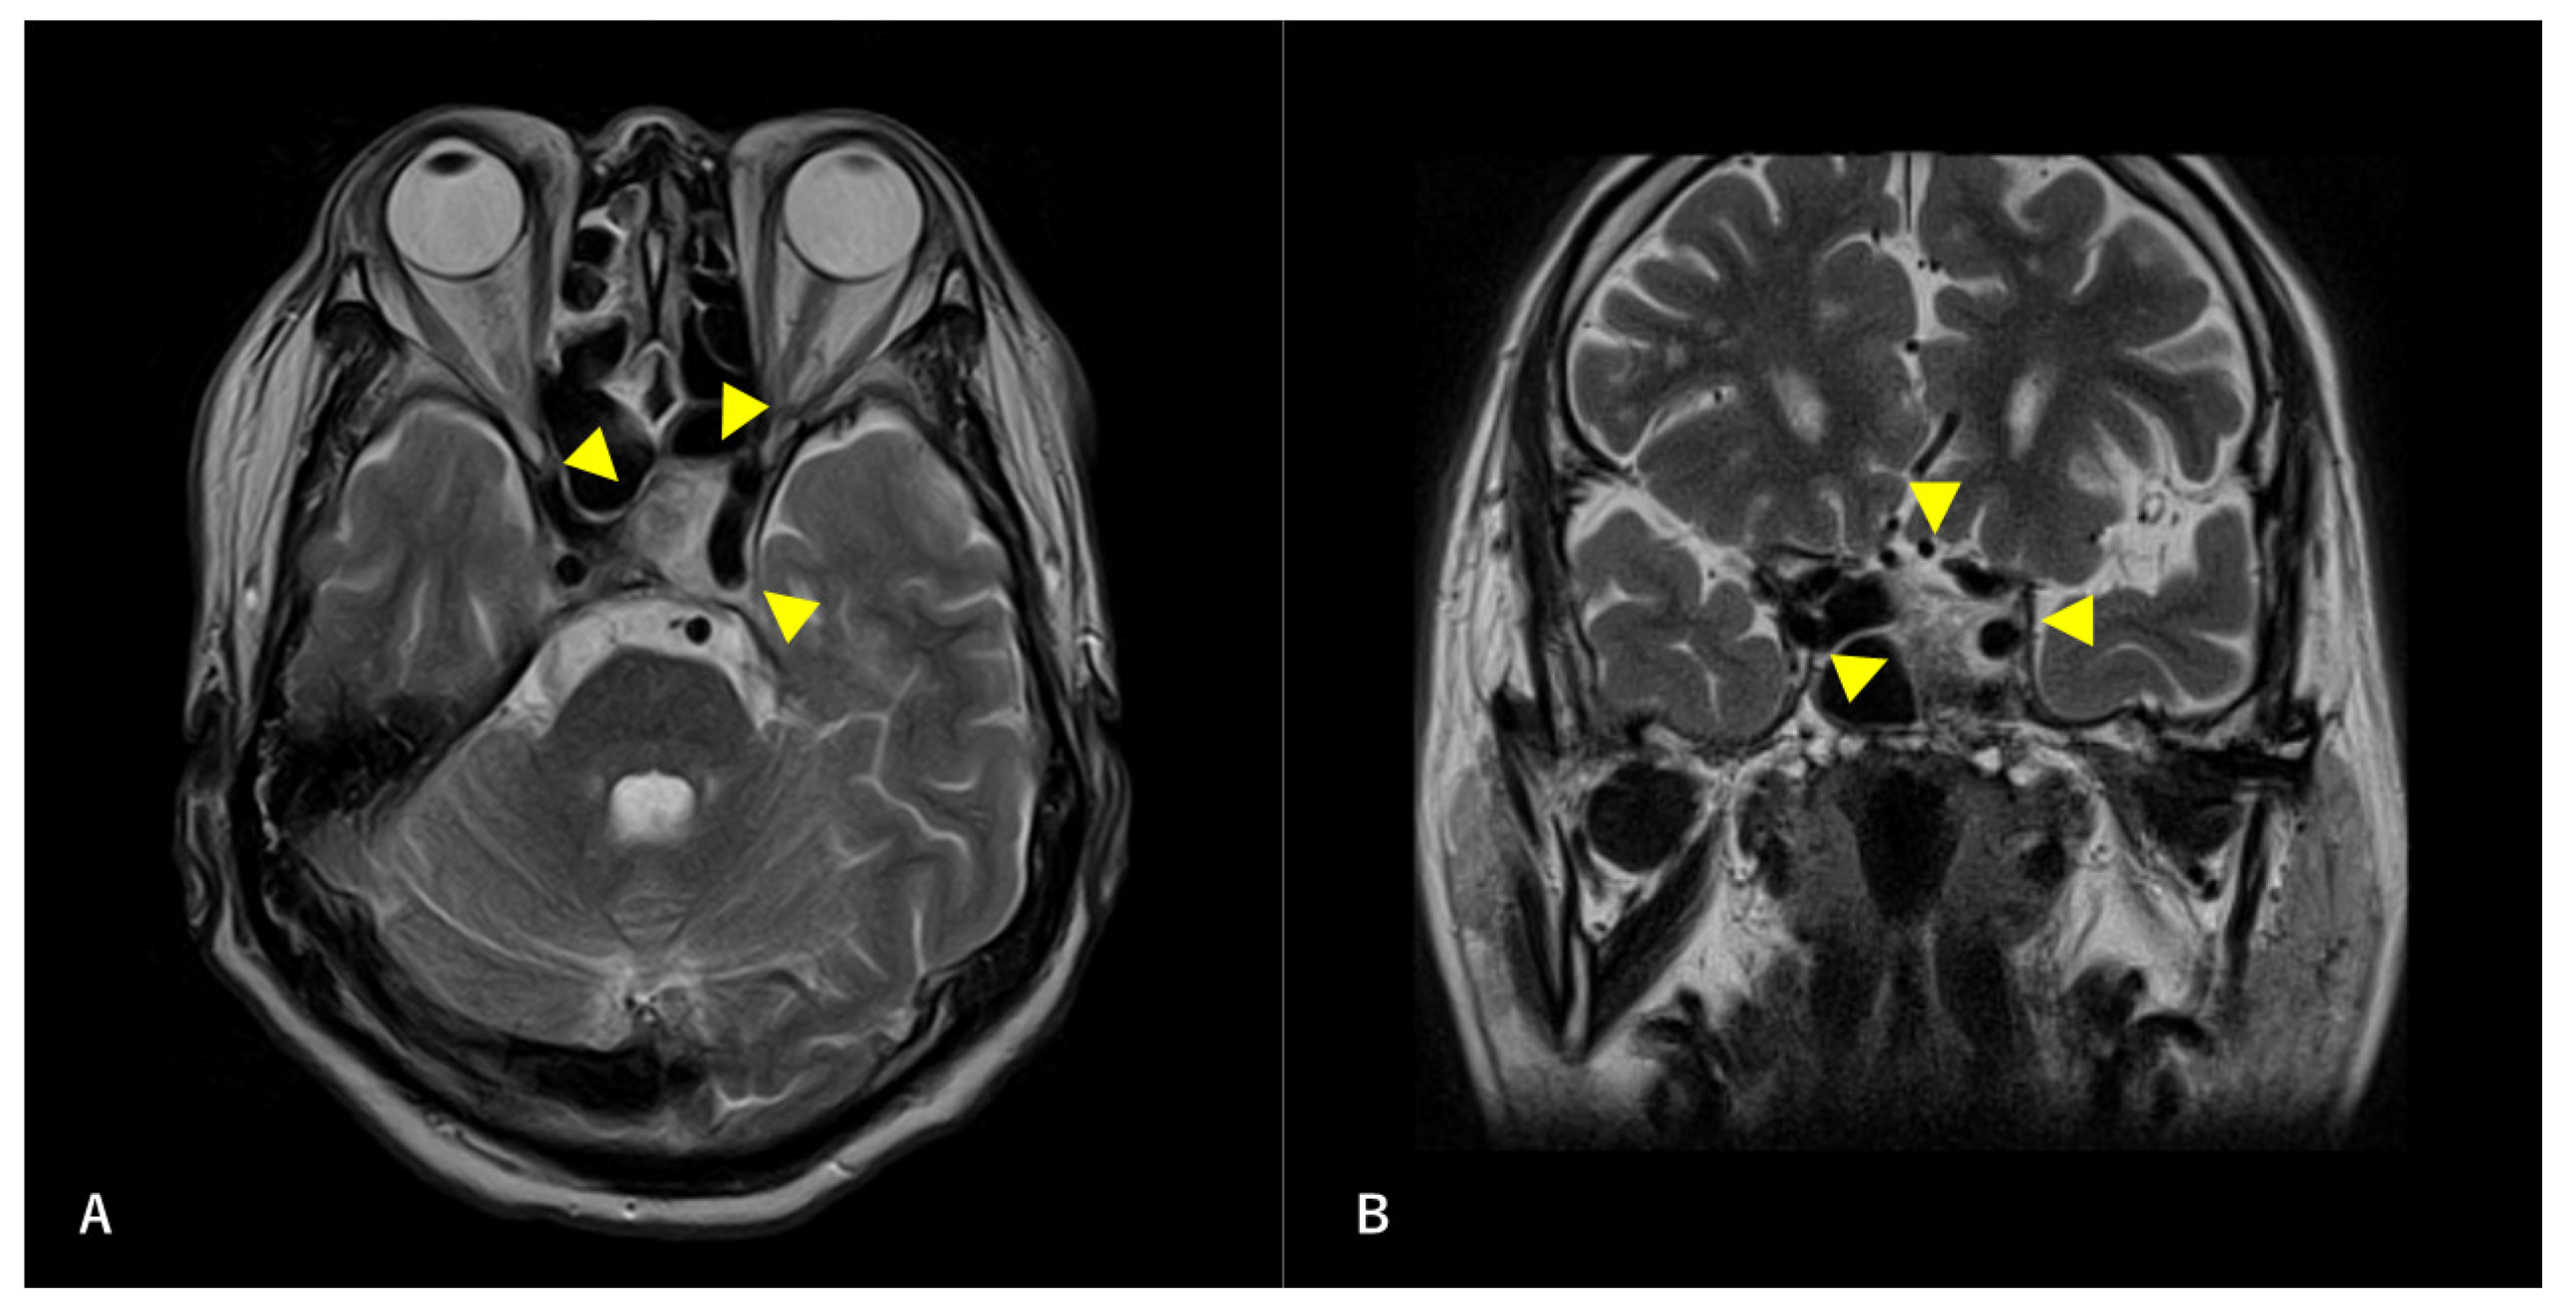

Figure 5. Postoperative magnetic resonance angiography (MRA) findings. MRA shows high-flow radial artery bypass between the M2 segment of the left middle cerebral artery (MCA) and the left cervical external carotid artery, with an additional superficial temporal artery (STA)–MCA bypass. Peripheral cerebral blood flow is maintained by the bypasses. The left internal carotid artery is trapped, and no blood flow is observed. Arrowheads indicate the high-flow bypass, and arrows indicate the STA–MCA bypass.

A multidisciplinary team of otolaryngologists and neurosurgeons performed a complete resection of the tumor using a simultaneous combined transcranial and transnasal approach that utilized high-flow radial artery bypass between the M2 segment of the left middle cerebral artery (MCA) and the left cervical external carotid artery with an additional superficial temporal artery–MCA bypass. The margin of tumor resection was determined by a rapid intraoperative diagnosis to confirm the tumor extent. The ICA was trapped under blood flow preservation bypasses, enabling complete resection of the tumor along with the ICA (Figure 4). The ocular artery and cranial nerves III–VI were preserved. The skull base was reconstructed using two layers of the temporalis muscle and a vascular pedicle nasoseptal flap. Magnetic resonance angiography was performed immediately after the surgery, indicating adequate blood flow through the bypasses (Figure 5). The postoperative immunohistochemistry results were positive, similar to the biopsy immunoprofile (Figure 6). In addition, there were no S-100 protein-positive sustentacular cells around the tumor cells. Differentiating between high-grade ONB and neuroendocrine tumors is sometimes difficult; the tumor was eventually diagnosed as NEC, based on the absence of sustentacular cells and the absence of morphological findings such as Homer–Wright rosettes (Figure 6D).